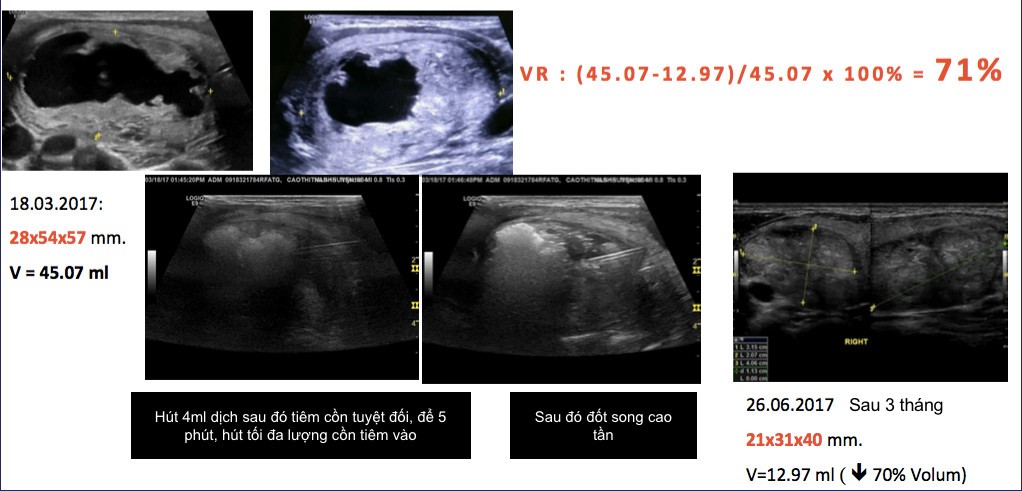

– Điều trị các khối lành tính tuyến giáp bằng tiêm cồn phối hợp với sóng cao tần (RFA) dưới hướng dẫn siêu âm là phương pháp phá hủy khối u tuyến giáp tại chỗ, kết hợp vừa hút dịch trong phần dạng nang và tiêm cồn tuyệt đối kết hợp với đốt sóng cao tần phần đặc để điều trị các khối hỗn hợp ở tuyến giáp gồm cả phần nang và phần đặc có tính chất lành tính.

– Dùng kim kích thước 18 hoặc 16G chọc qua eo tuyến giáp vào các tổn thương dạng nang trong khối, hút hết dịch trong nang sau đó bơm cồn tuyệt đối để lưu lại trong cấu trúc dạng nang từ 2-5 phút. Sau đó cố gắng hút tối đa lượng cồn trong tổn thương.

– Cắm kim đốt sóng cao tần vào tổn thương qua eo tuyến giáp và tiến hành đốt tổn thương bằng kỹ thuật di chuyển “moving technique”, từng phần một trên nguyên từng phần cắm kim từ phần sâu nhất rồi rút ra phần nông của tổn thương.

– Tiến hành đốt dần từng phần một cho tới khi diện đốt bao phủ gần toàn bộ tổn thương.

– Bệnh nhân được hẹn kiểm tra lại vào các thời điểm 1 tháng, 3 tháng, 6 tháng và sau 1 năm, đánh giá đáp ứng điều trị bằng đo thể tích khối tuyến giáp. Thông thường khối tuyến giáp giảm 30-60% thể tích sau 1 tháng và 50-90% sau 6 tháng, cải thiện hẳn triệu chứng thẩm mỹ.